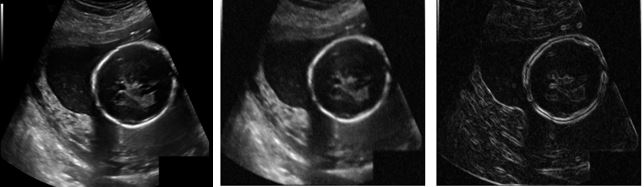

Hybrid Technique for Estimating Fetal Head Circumference Using Ultrasound Imaging

Ameera Shafique, Zobia Suhail, Hafiz Muhammad Danish

1058-1075